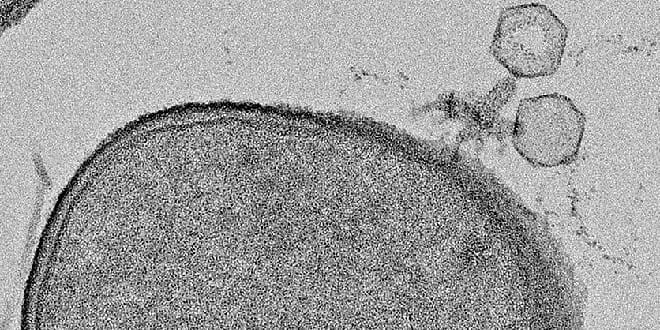

Viruses – like COVID-19 – are viruses, while bacteria are bacteria. We have long thought that they have nothing to do with each other, even though a viral infection can weaken the body and allow bacteria to attack the body as well.

While both can cause disease, viruses are not living organisms, whereas bacteria are. Viruses are only active within host cells which they need to reproduce, while bacteria are single-celled organisms that produce their own energy and can reproduce on their own.

Bacteria are huge compared to viruses, and the two types of pathogens differ in how they cause infection. Systemic diseases caused by viral infection include influenza, measles, polio, AIDS, and COVID-19. Pathogenic bacteria can cause pneumonia, tetanus, tuberculosis, food poisoning and more.

These differ from the kind that infect humans in their choice of targets, but they all consist of genetic material – DNA or RNA – that hijacks parts of the host’s replication machinery to make copies of themselves and spread.